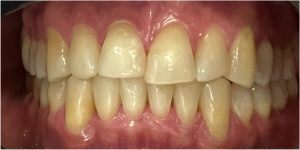

Pod opieką Agnieszki Łukowicz, Master of Science Orthodontics została poddana zaawansowanemu leczeniu aparatem stałym ligaturowym, Dzięki czemu udało się osiągnąć znaczące zmiany:

poszerzenie luków zębowych,

korekta tyłozgryzu,

rozwiązanie stłoczenia,

odrotowanie zrotowanych zębów,

odbudowa startych zębów.

Efekt estetyczny został dopełniony przez wybielanie zębów i odbudowę kompozytową wykonaną przez dr Monikę Niewitecką.

Przedstawiamy piękny i zdrowy uśmiech naszej Pacjentki!